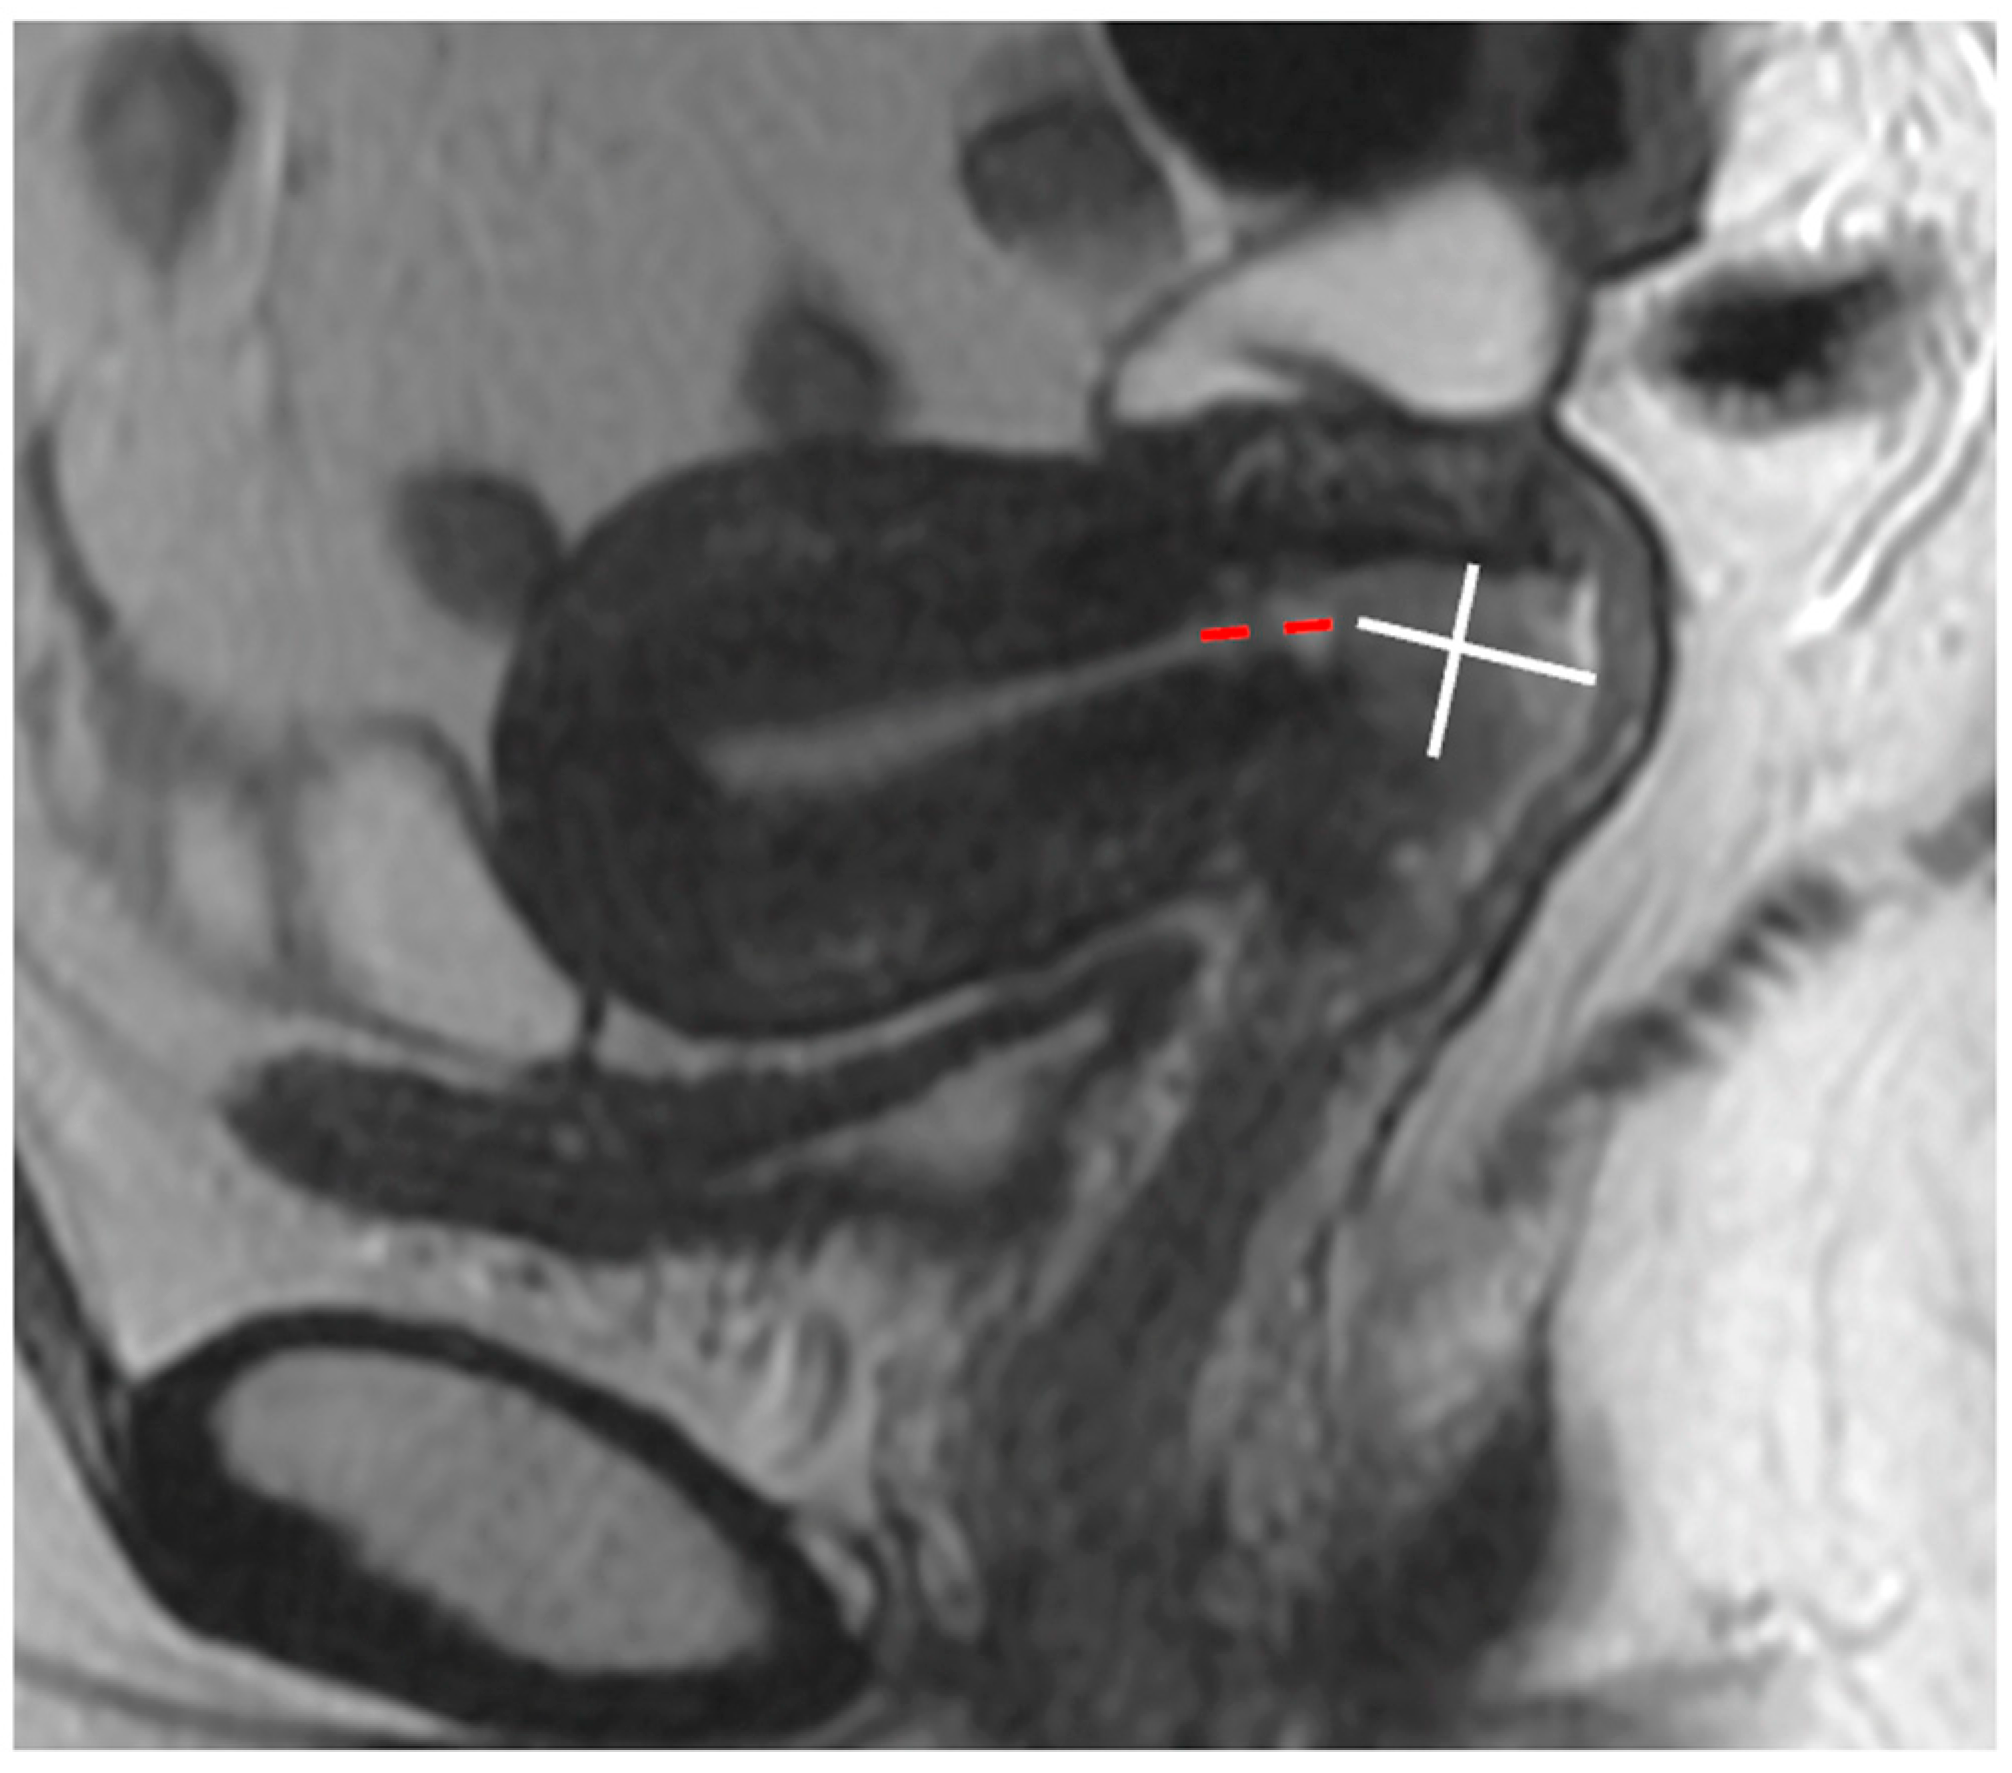

- Salvo, G.; Odetto, D.; Saez Perrotta, M.C.; Noll, F.; Perrotta, M.; Pareja, R.; Wernicke, A.; Ramirez, P.T. Measurement of tumor size in early cervical cancer: An ever-evolving paradigm. Int. J. Gynecol. Cancer 2020, 30, 1215–1223. [Google Scholar] [CrossRef] [PubMed]

- Kido, A.; Nakamoto, Y. Implications of the new FIGO staging and the role of imaging in cervical cancer. Br. J. Radiol. 2021, 94, 20201342. [Google Scholar] [CrossRef] [PubMed]

- Young, P.; Daniel, B.; Sommer, G.; Kim, B.; Herfkens, R. Intravaginal gel for staging of female pelvic cancers--preliminary report of safety, distention, and gel-mucosal contrast during magnetic resonance examination. J Comput. Assist. Tomogr. 2012, 36, 253–256. [Google Scholar] [CrossRef] [PubMed]

| Small FOV Sagittal T2WI | Accurate tumour size, local staging (e.g., vaginal, bladder, rectal invasion) |

| Small FOV Axial oblique T2WI | Local staging, parametrial and pelvic sidewall involvement |